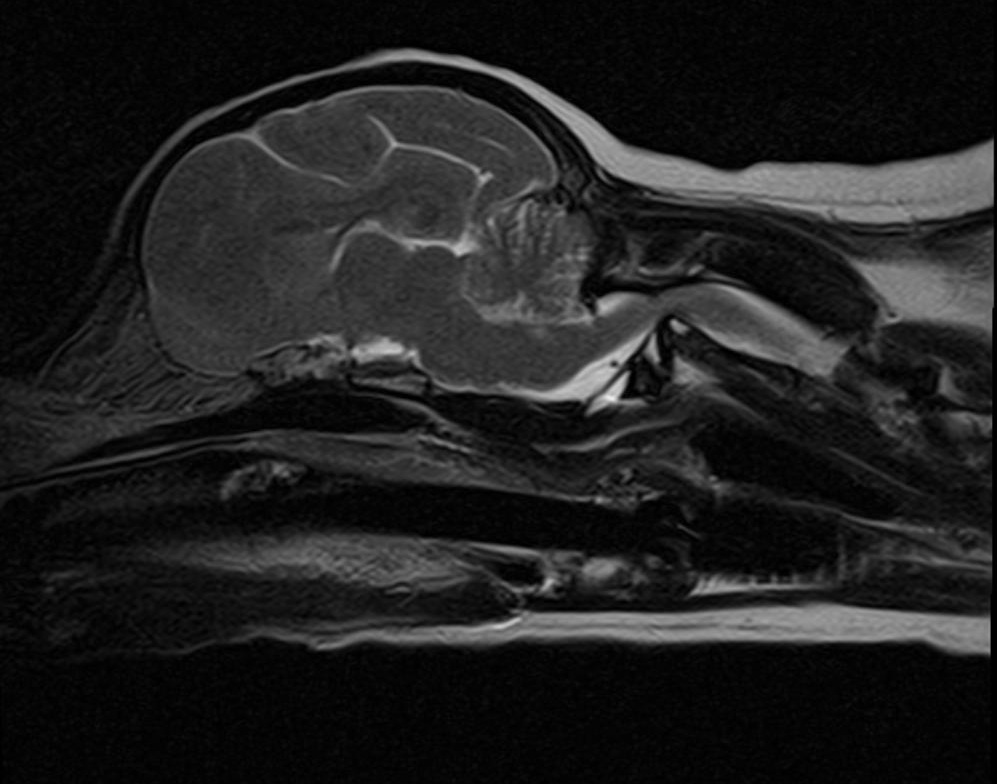

Q. This is a 10-month old 8kg female spayed mixed breed dog who presented for evaluation of tetraparesis and episodic neck pain of 3 months duration. What is your diagnosis?

A. Atlantoaxial subluxation. The post-operative radiographs are shown below. Note the absence of the dens.